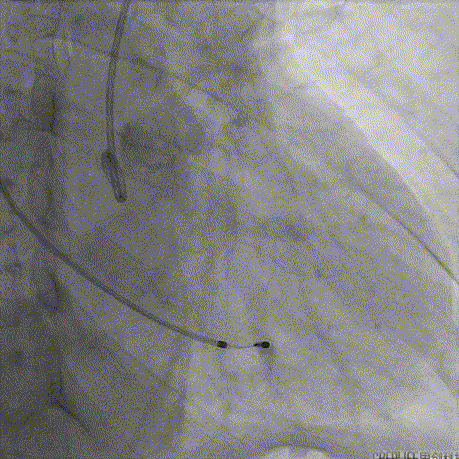

释放到工作位后多角度观察左右冠脉血流灌注情况、瓣膜释放形态及植入深度,确认没问题后再缓慢脱钩完全释放,最终造影显示瓣膜形态、位置良好,冠脉血流灌注正常,微少量瓣周漏;

瓣膜缓慢脱钩完全释放

术后根部造影

术后外周血管造影检查,确认未产生血管并发症。